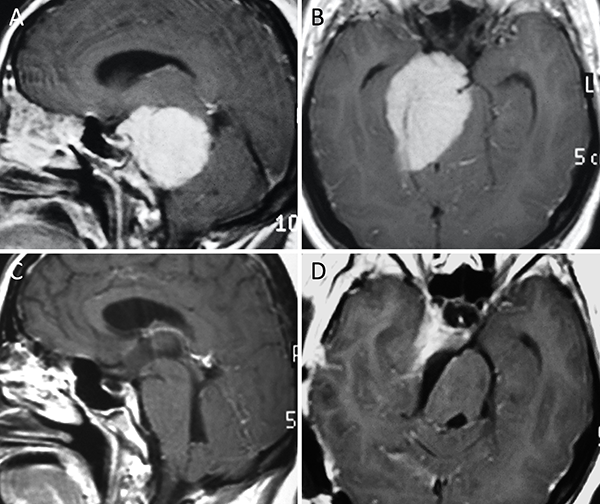

Figura 11. Meningioma del foramen magno posterior. A-B: RM preoperatoria; C-D: RM postoperatoria.